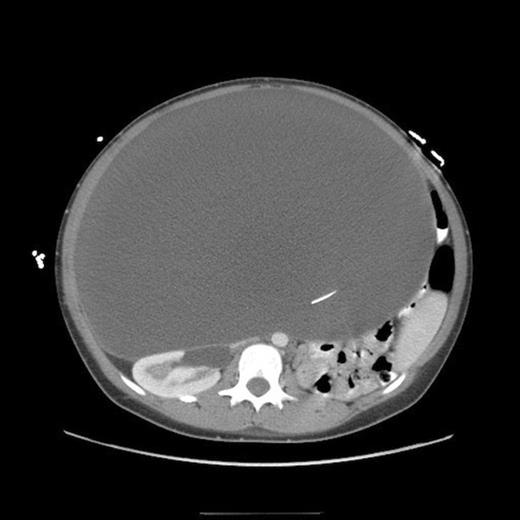

Post-operative abdominal CT demonstrating complete resolution of the fluid compartment

The patient underwent laparoscopic cyst drainage with removal of the cyst wall. A total of 12.7L of fluid was drained. Culture results and routine labs were all negative. A post-operative CT demonstrated complete resolution of the fluid compartment (Fig. 4). The VP shunt catheter was initially left in the abdominal cavity. One month later, however, she developed significant recurrence of fluid collection (Fig. 5) and lethargy from malfunction of the VP shunt. The recurrent fluid was drained under ultrasound guidance, and her abdominal shunt catheter was removed. A new shunt catheter was placed in the right atrium, and the patient made a full recovery without any further complications.